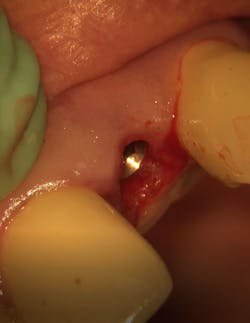

First visit: Extraction and immediate implant placement, immediate placement of the final abutment prepared intraorally, and then a provisional out of function.

Maintaining initial stability is important when an implant is placed in a compromised extraction site, since there is less bone-to-implant contact there than in a healed site. Because of its architecture, the Ditron Ultimate implant offers a very high initial stability and strong abutment connection. The implant profile uniformly distributes the stress directly to the bone, which results in a more even distribution of force and lower long-term crestal resorption. This implant system has a good aggressive thread profile and a secure abutment connection, which are both key characteristics. The microthreads on the implant’s reverse conical neck (RCN) greatly increase the implant’s ability to resist axial displacement, and the mechanical stimulus the microthreads provide helps to preserve the peri-implant marginal bone. By inserting an Ultimate implant, 5.57 mm3 of bone will be saved compared to that of a non-RCN implant.7